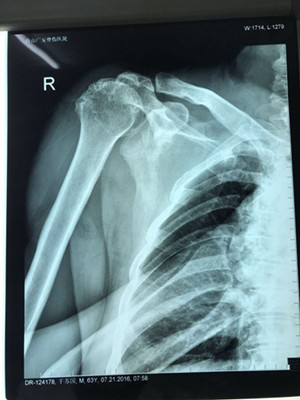

據(jù)了解,干大伯半年前因外傷導(dǎo)致頸椎外傷伴截癱,右肩關(guān)節(jié)脫位伴巨大肩袖斷裂,曾在廣安醫(yī)院接受頸椎手術(shù),術(shù)后恢復(fù)良好。后來,干大伯要求進一步對肩關(guān)節(jié)進行治療。廣安醫(yī)院副院長危立軍及運動醫(yī)學(xué)科主任羅軍對其進行詳細(xì)檢查后,認(rèn)為干大伯的右肩存在巨大不可修復(fù)肩袖撕裂伴嚴(yán)重的關(guān)節(jié)炎,肩袖的脂肪浸潤達(dá)到四級,治療上有一定的挑戰(zhàn)性,只能通過特殊類型的人工肩關(guān)節(jié)——反式全肩人工關(guān)節(jié)來重建關(guān)節(jié)功能。